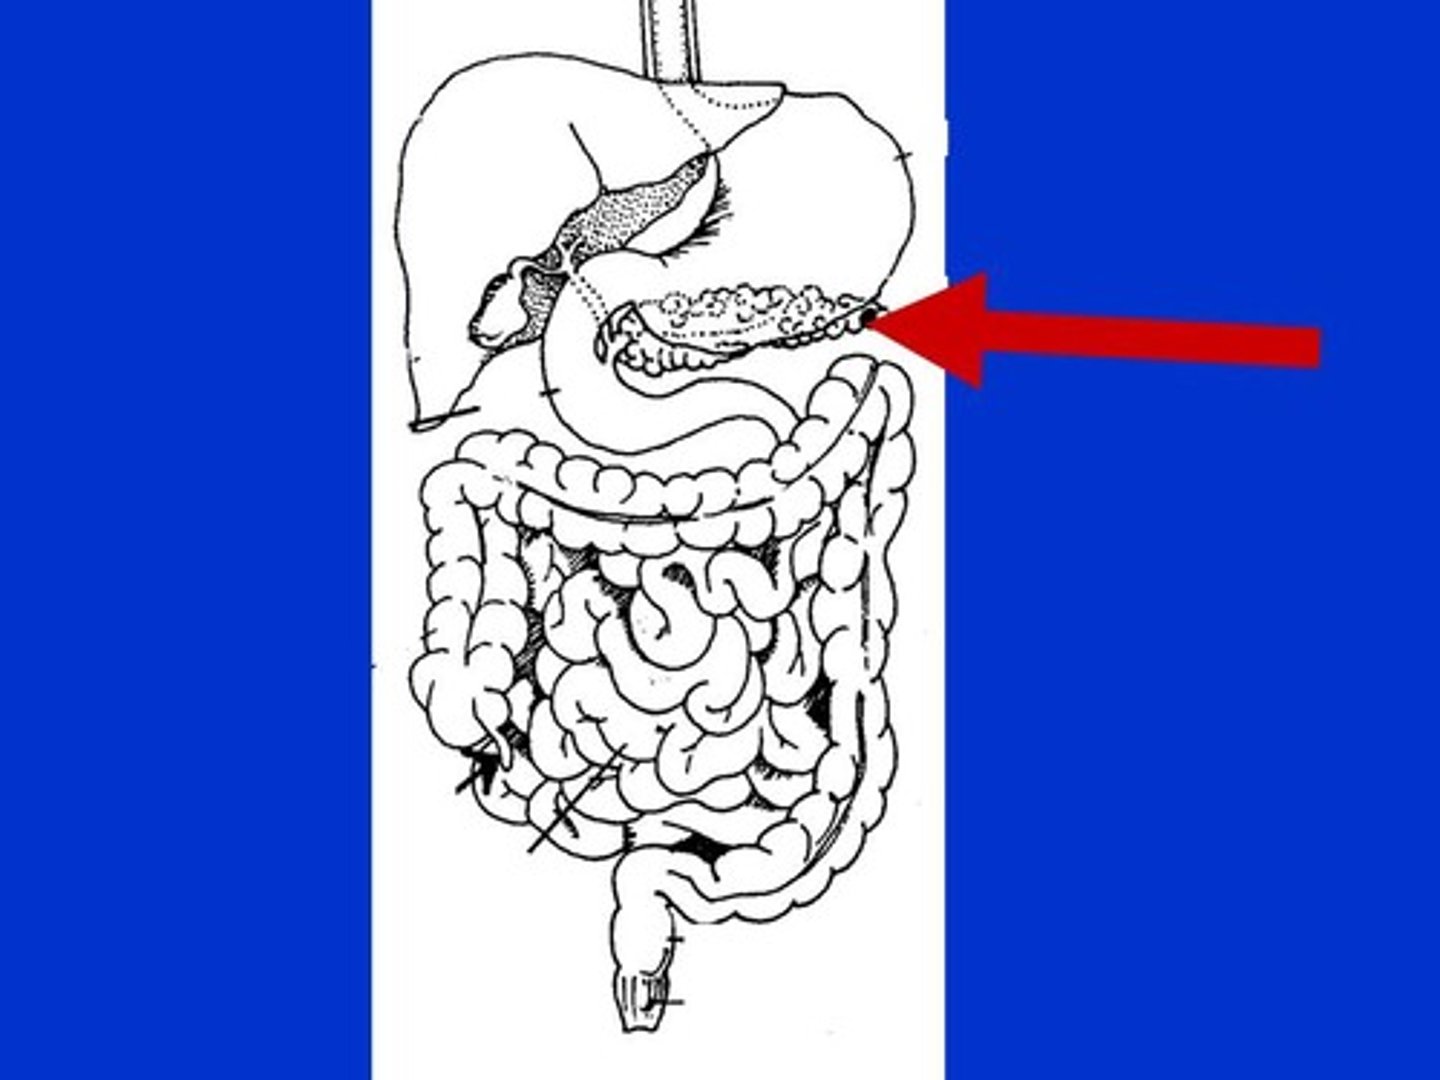

Pancreas

An organs in the abdominal cavity that is deep to the stomach

Pancreas hormones

insulin and glucagon